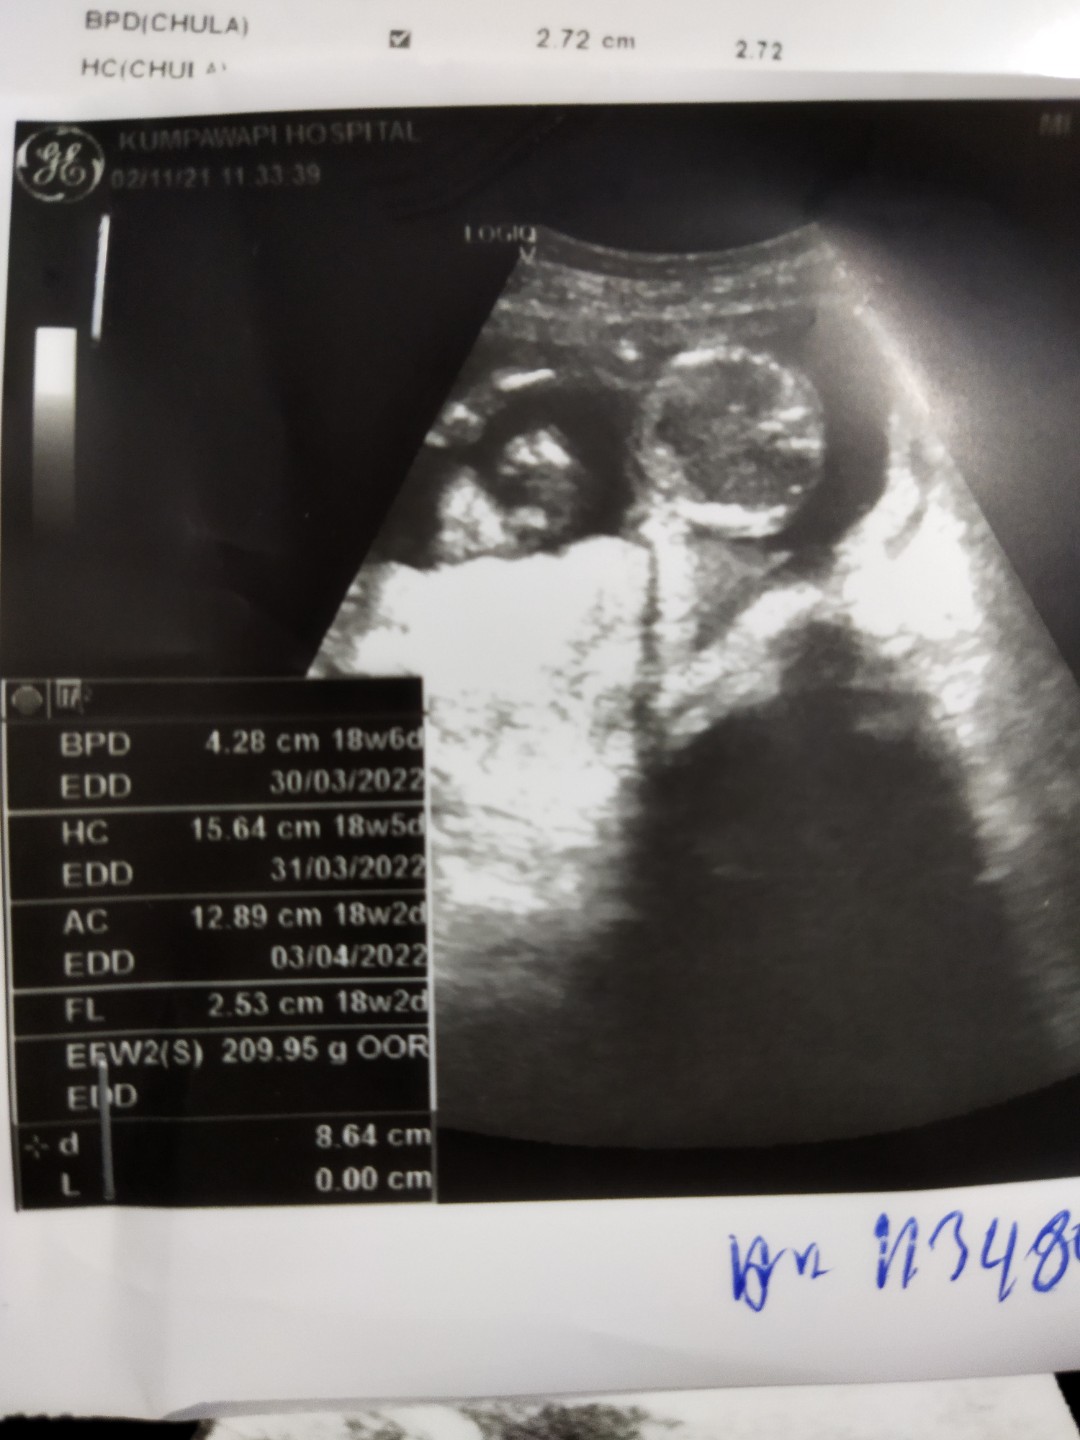

ซาวตอน14wค่ะ ตอนนี้19wแล้ว ทีมมีนาค่ะ🥰

14w 3d นัดผ่าคลอด 21 มีนา 65 ยังไม่รู้เพศเลย ... 😘